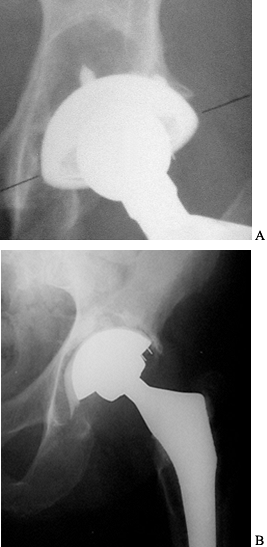

![]() |

Figure 106.2. A: Focal osteolysis in the supracetabular region. Cup remains stable. B: Linear osteolysis leading to an unstable cup.

not constitute an indication for surgery by itself. Loose, symptomatic

surgery if osteolysis is progressive. Because osteolysis is usually

asymptomatic until component stability is compromised, routine

follow-up evaluation is appropriate. Osteolytic lesions can be bone

grafted with an exchange of the acetabular liner and femoral head at an

early stage (65) (Fig. 106.4). Limited surgery becomes less feasible as the lesion enlarges.

Figure 106.4. A: Polyethylene wear leading to large supra-acetabular lesion. Note asymmetric position of the head in the cup. B: Cup is stable; therefore, retained and osteolytic lesion grafted with good results.